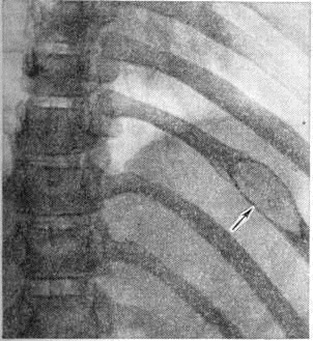

Солитарная форма (солитарная миелома) наблюдается ещё реже; одни исследователи, например А. С. Рейнберг, рассматривают эту форму как раннюю фазу Миеломная болезнь, другие — как самостоятельное заболевание (первичную опухоль костного мозга, обладающую всеми признаками опухолевого роста). Солитарные миеломы чаще всего возникают в костях таза (обычно в крыле подвздошной кости), позвоночнике, костях свода черепа, ребрах, реже в проксимальном отделе плечевой или бедренной кости. Рентгенологически можно выделить две разновидности этой формы: классический чисто деструктивный крупный солитарный костный дефект, чётко отграниченный от окружающей ткани (рисунок 12), и кистознотрабекулярную миелому — крупное кистовидное или ячеистое образование (рисунок 13). Реактивного склероза в окружности опухолевого узла обычно нет. В редких случаях солитарная миелома может наблюдаться в других органах и тканях. Солитарная миелома желудка рентгенологически даёт картину, сходную с инфильтративным раком или лимфогранулематозом желудка.

Рис. 12. | ||

Разнообразие рентгенологическое проявлений Миеломная болезнь требует проведения дифференциальной диагностики с другими заболеваниями. Наибольшие трудности возникают в дифференциальной диагностике множественно-очаговой формы миеломы с метастазами рака в кости. Дифференцирование основывается на комплексе клинико-лабораторных и рентгенологическое данных. Миеломные узлы чаще всего располагаются в рёбрах и грудине, не вызывают в отличие от раковых метастазов периостальной реакции и остеосклероза.